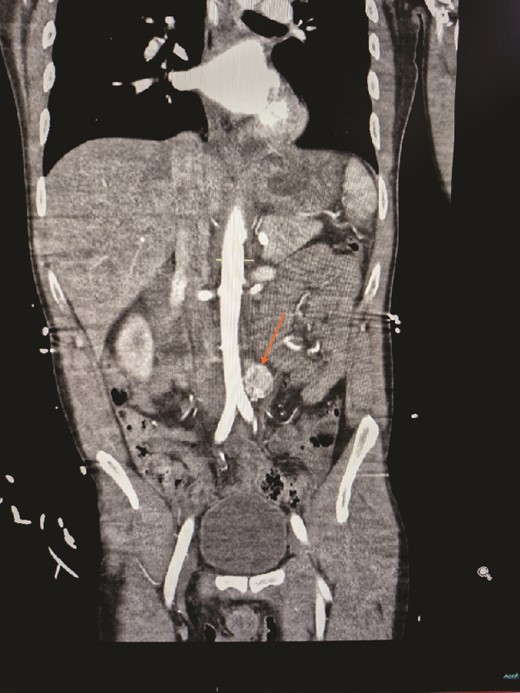

A 30-year-old urology registrar presented to the emergency department complaining of headache, nausea and abdominal pain, and was found to be hypertensive. He became very agitated whilst on the ward and was intubated. A computed tomography (CT) of the brain was normal, but subsequent CT of his abdomen and pelvis revealed a 2 × 2 × 3 cm hypervascular mass adjacent to his aorta just above the bifurcation. Initially suspected to be an aneurysm, it was later identified as a paraganglioma (Figs 1 and 2). He was then referred to the endocrine surgery team.

Contrasted CT of the abdomen and pelvis in arterial phase, coronal plane, revealed a similar mass, contrast enhanced heterogenous lesion with well demarcated borders, measuring ⁓2 × 2 × 3 cm, situated at the left para-aortic region.